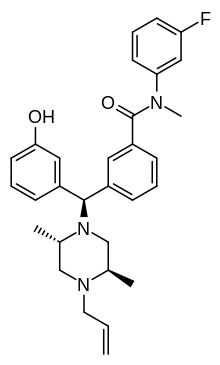

Diphenylmethylpiperazines